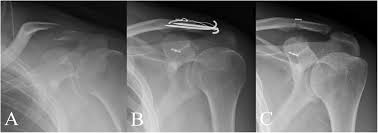

الأشعة السينية

الطريقة الأساسية للتحقق من وجود كسر الترقوة هو عن طريق الأشعة السينية من الترقوة من أجل تحديد نوع الكسر ومدى الإصابة في معظم الحالات، سيتم اتخاذ الأشعة السينية كلا من عظام الترقوة لأغراض المقارنة.

تحدد الأشعة السينية مدى كسر الترقوة، وتحديد موقعها وتحديد ما إذا كان هناك إصابة في المفاصل.

العلاج الجراحي

يعمل عملية جراحية في40٪ من الحالات غالبًا ما يتم إزاحة الكسور من النوع الثاني وقد يكون لها معدل أعلى من عدم الالتئام.

معدلات عدم الالتحام التي تم الإبلاغ عنها بعد العلاج غير الجراحي لكسور الترقوة البعيدة من النوع الثاني تتراوح من 28٪ إلى 44٪ وعادة ما تتضمن جراحة الترقوة المكسورة وضع أجهزة تثبيت .

- شرائح

- أو مسامير

- أو قضبان

- او تقنية الأزرار الداخلية المزدوجة ذات الحلقة المغلقة ذات الحد الأدنى من التدخل الجراحي

للحفاظ على الوضع الصحيح للعظام أثناء التئامها.